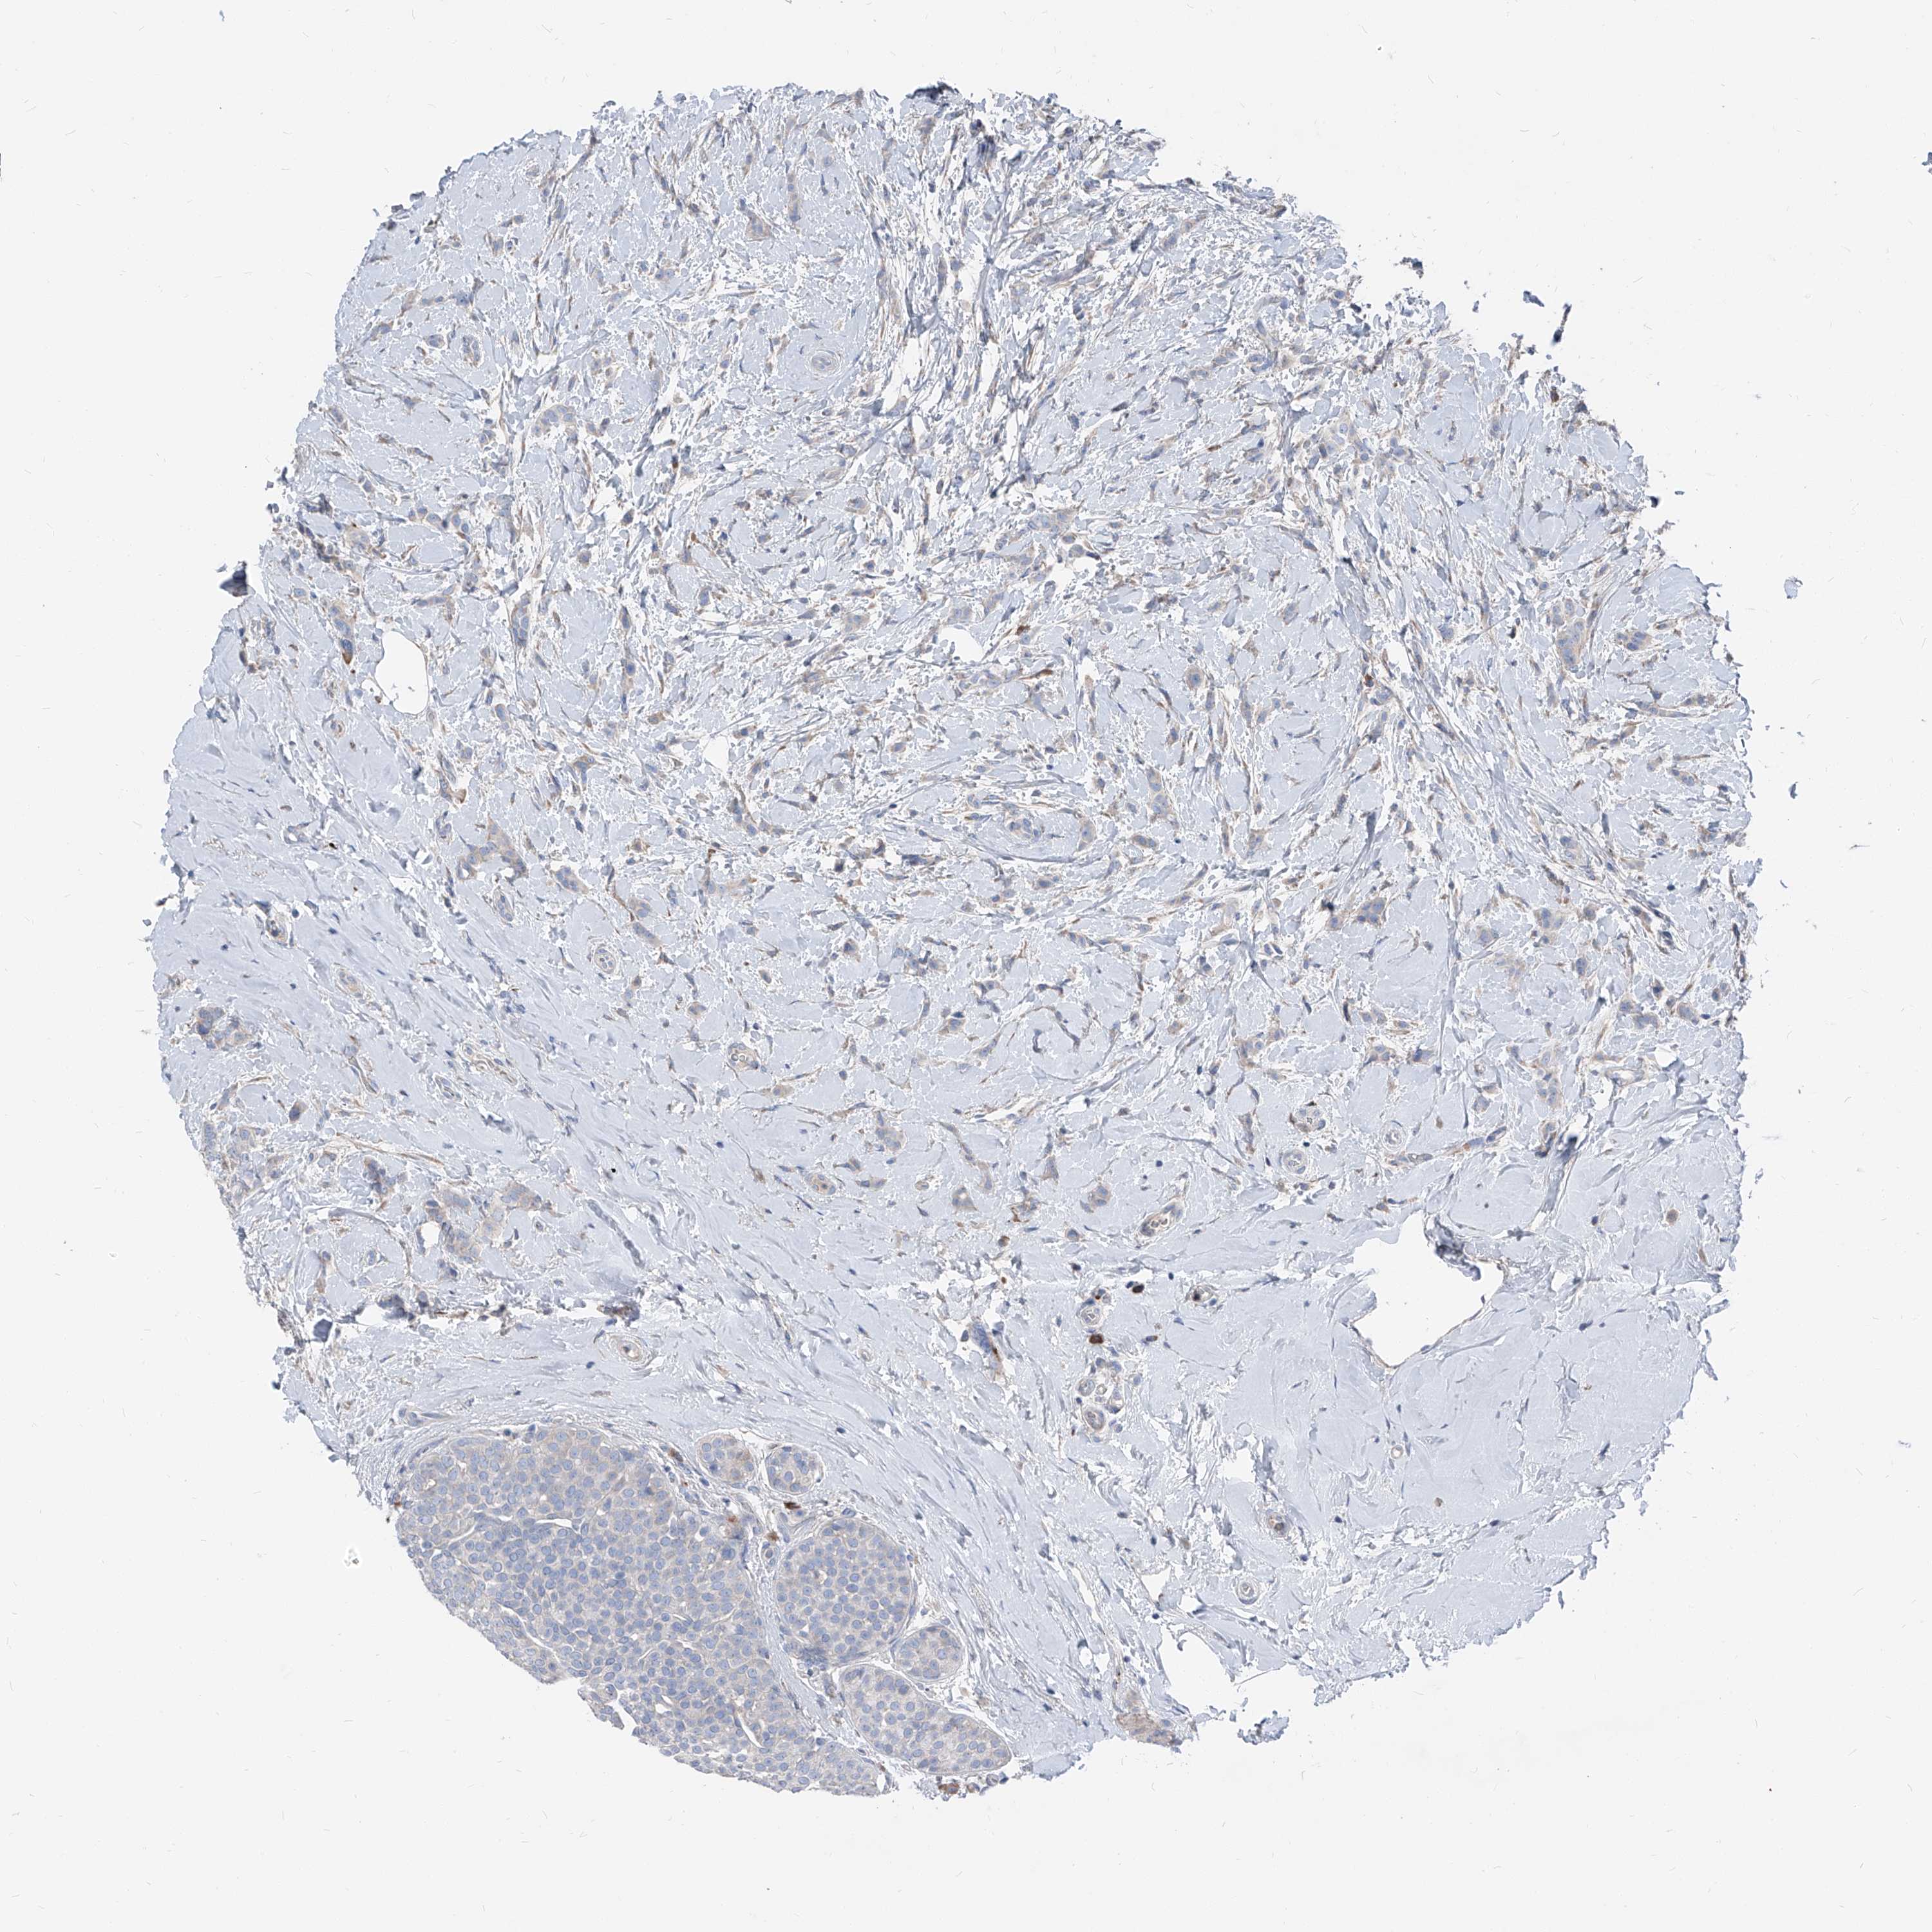

CANCER BREAST CANCER Show tissue menu

BRCA TCGA BRCA VALIDATION PROTEIN EXPRESSION

Breast cancer

Human cancer